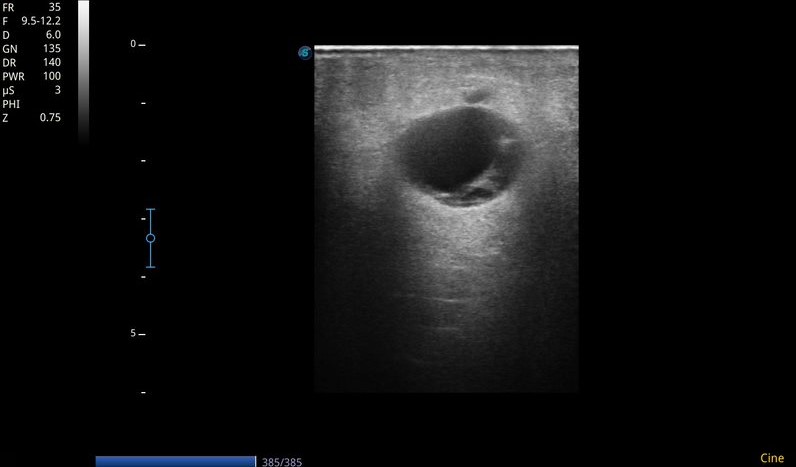

Ecografía MII: Sistema venoso profundo permeable, compresible en todo su recorrido, sin contenido hiperecogénico en su interior. Sistema venoso superficial permeable. Se objetiva a nivel de tejido celular subcutáneo de región interna de tercio superior de muslo izquierdo, colección anecoica, tabicada, no vascularizada, con algunos ecos en su interior, de unos 3-4 cm, con sombra acústica posterior. Importante edema en empedrado en pierna izquierda compatible con celulitis.

• Punción de colección: Extracción de contenido seroso.